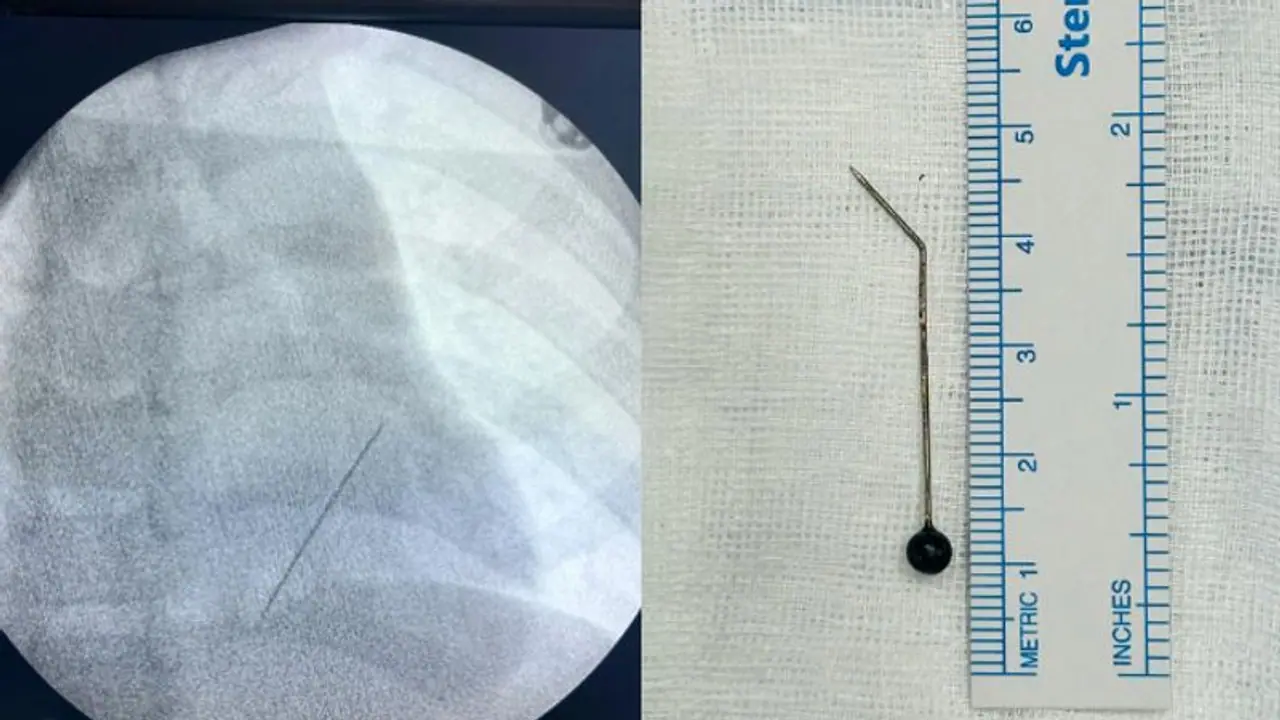

കൊച്ചി: കളിക്കുന്നതിനിടെ അബദ്ധത്തിൽ വിഴുങ്ങിയ സൂചി 7 വയസ്സുകാരന്റെ ശ്വാസകോശത്തിൽ നിന്ന് പുറത്തെടുത്തു. മാലിദ്വീപ് സ്വദേശിയായ കുട്ടി ഈ മാസം 22 നാണ് വസ്ത്രങ്ങളിൽ ഉപയോഗിക്കുന്ന വലിയ സൂചിയായ ഹിജാബ് പിൻ കളിക്കുന്നതിനിടെ അബദ്ധത്തിൽ വിഴുങ്ങിയത്. ഇതേ തുടർന്ന് രക്തസ്രാവം അനുഭവപ്പെട്ട കുട്ടിയെ ഉടൻ തന്നെ മാലിദ്വീപിലുള്ള ഇന്ദിരാഗാന്ധി മെമ്മോറിയൽ ഹോസ്പിറ്റലിൽ എത്തിച്ചു. ഇവിടെ നടന്ന എക്സ്റേ പരിശോധനയിലാണ് സൂചി അപകടകരമായ നിലയിൽ ഇടതുവശത്തെ ശ്വാസകോശത്തിന്റെ ഏറ്റവും അടിത്തട്ടിൽ ലോവർ ലോബിനോട് ചേർന്ന് തിരശ്ചീനമായി കിടക്കുന്നതായി കണ്ടെത്തിയത്.

കടുത്ത ചുമയും രക്തസ്രാവവും തുടരുന്നതിനിടെ കുട്ടിയെ വിദഗ്ധ ചികിത്സയ്ക്കായി അടിയന്തരമായി ഹെലികോപ്റ്ററിൽ മാലിദ്വീപിൽ നിന്ന് കൊച്ചിയിലേക്കെത്തിക്കുകയായിരുന്നു. കൊച്ചി അമൃത ആശുപത്രിയിൽ ചീഫ് ഇന്റർവെൻഷണൽ പൾമണോളജിസ്റ്റ് ഡോ.ടിങ്കു ജോസഫിന്റെ നേതൃത്വത്തിലാണ് കുട്ടിയുടെ ശ്വാസകോശത്തിൽ കുടുങ്ങിയ 5 സെന്റിമീറ്ററോളം നീളമുള്ള സൂചി റിജിഡ് ബ്രോങ്കോസ്കോപിയിലൂടെ പുറത്തെടുത്തത്. മൂന്നരമണിക്കൂറോളം നീണ്ട റിജിഡ് ബ്രോങ്കോസ്കോപ്പി നടപടിക്രമത്തിലൂടെയാണ് ഒടുവിൽ സൂചി പുറത്തെടുത്തത്. മറ്റ് അപകടസാധ്യതകൾ ഒഴിവാക്കാൻ സൂചിയുടെ അഗ്രഭാഗം ശ്വാസകോശത്തിനുള്ളിൽ വച്ച് തന്നെ ചെറുതായി വളച്ച ശേഷമാണ് സൂചി പുറത്തെടുത്തത്.

ഹൃദയത്തിലേക്കുള്ള പ്രധാന രക്തക്കുഴലുകൾക്ക് തൊട്ടടുത്തായാണ് സൂചി കുടുങ്ങിക്കിടന്നിരുന്നത് എന്നത് വലിയ വെല്ലുവിളിയായിരുന്നെന്നും, ഇത്രയും നീളത്തിലുള്ള സൂചി ഓപ്പൺ സർജറി കൂടാതെ, റിജിഡ് ബ്രോങ്കോസ്കോപിയിലൂടെ പുറത്തെടുക്കുന്നത് അപൂർവമാണെന്നും ഡോ.ടിങ്കു ജോസഫ് പ്രതികരിക്കുന്നത്. ആശുപത്രിയിൽ നിന്ന് ഡിസ്ചാർജായ കുട്ടി മാതാപിതാക്കൾക്കൊപ്പം ഞായറാഴ്ച മാലിദ്വീപിലേക്ക് മടങ്ങും.